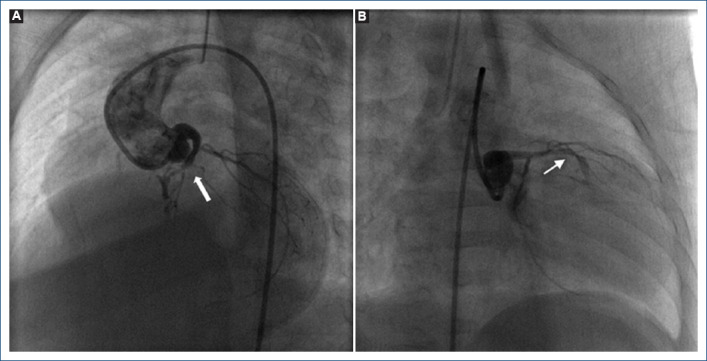

Objective: Pulmonary atresia with intact ventricular septum (PA-IVS) is a rare congenital heart disease characterized by a wide morphological spectrum that can be associated with abnormalities in the coronary circulation such as sinusoids, fistulas, stenosis or atresia. Some patients do not present ventriculo-coronary fistulas or intramyocardial sinusoids, other patients do present ventriculo-coronary connections, but only some of the latter will have right ventricle-dependent coronary circulation (RVDCC); timely establishment of the diagnosis of RVDCC is essential, since the prognosis of these patients is generally fatal. There are reports of patients with this type of coronary circulation (RVDCC) who were undergone to univentricular physiology, but this treatment option remains controversial, so the purpose of this manuscript is to share three cases with PA-IVS and RVDCC, their outcome and the reflections they provide us.

Results: Three patients were identified, the clinical and angiographic characteristics and their evolution are described, and a new technique or maneuver for transient percutaneous decompress of the right ventricle is described theoretically for those cases where there is doubt about RVDCC during the angiographic study.

Conclusions: An accurate diagnosis regarding the existence of RVDCC is vital. In some cases, the interpretation of angiography for the diagnosis of RVDCC can be difficult to pinpoint and in many cases, it can be operator dependent, however we consider that is necessary to have a technique or maneuver that can objectively and without doubts determine RVDCC in those cases where angiography is not totally conclusive and thus be able to offer the best therapeutic option.